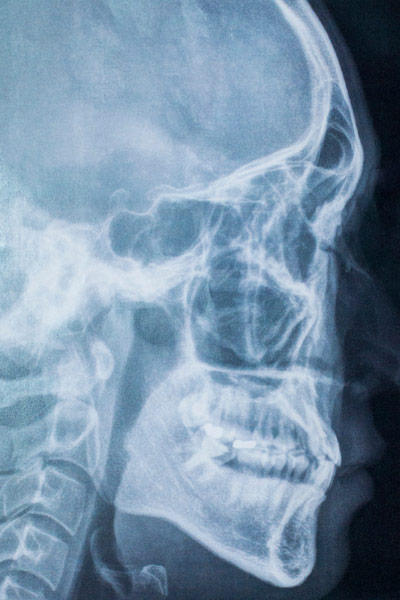

Cone Beam CT 3D Scanner

Cone Beam CT Scan

A cone beam CT scan is a diagnostic tool that produces a 3D representation of your teeth, gums, nerve pathways, and underlying bone structure within a single image. We typically utilize cone beam CT scans when a regular x-ray is not enough. Cone beam CT scans are ideal for surgical planning, the diagnosis of TMJ disorders and tumors, and the evaluation of bone structure and tooth orientation.